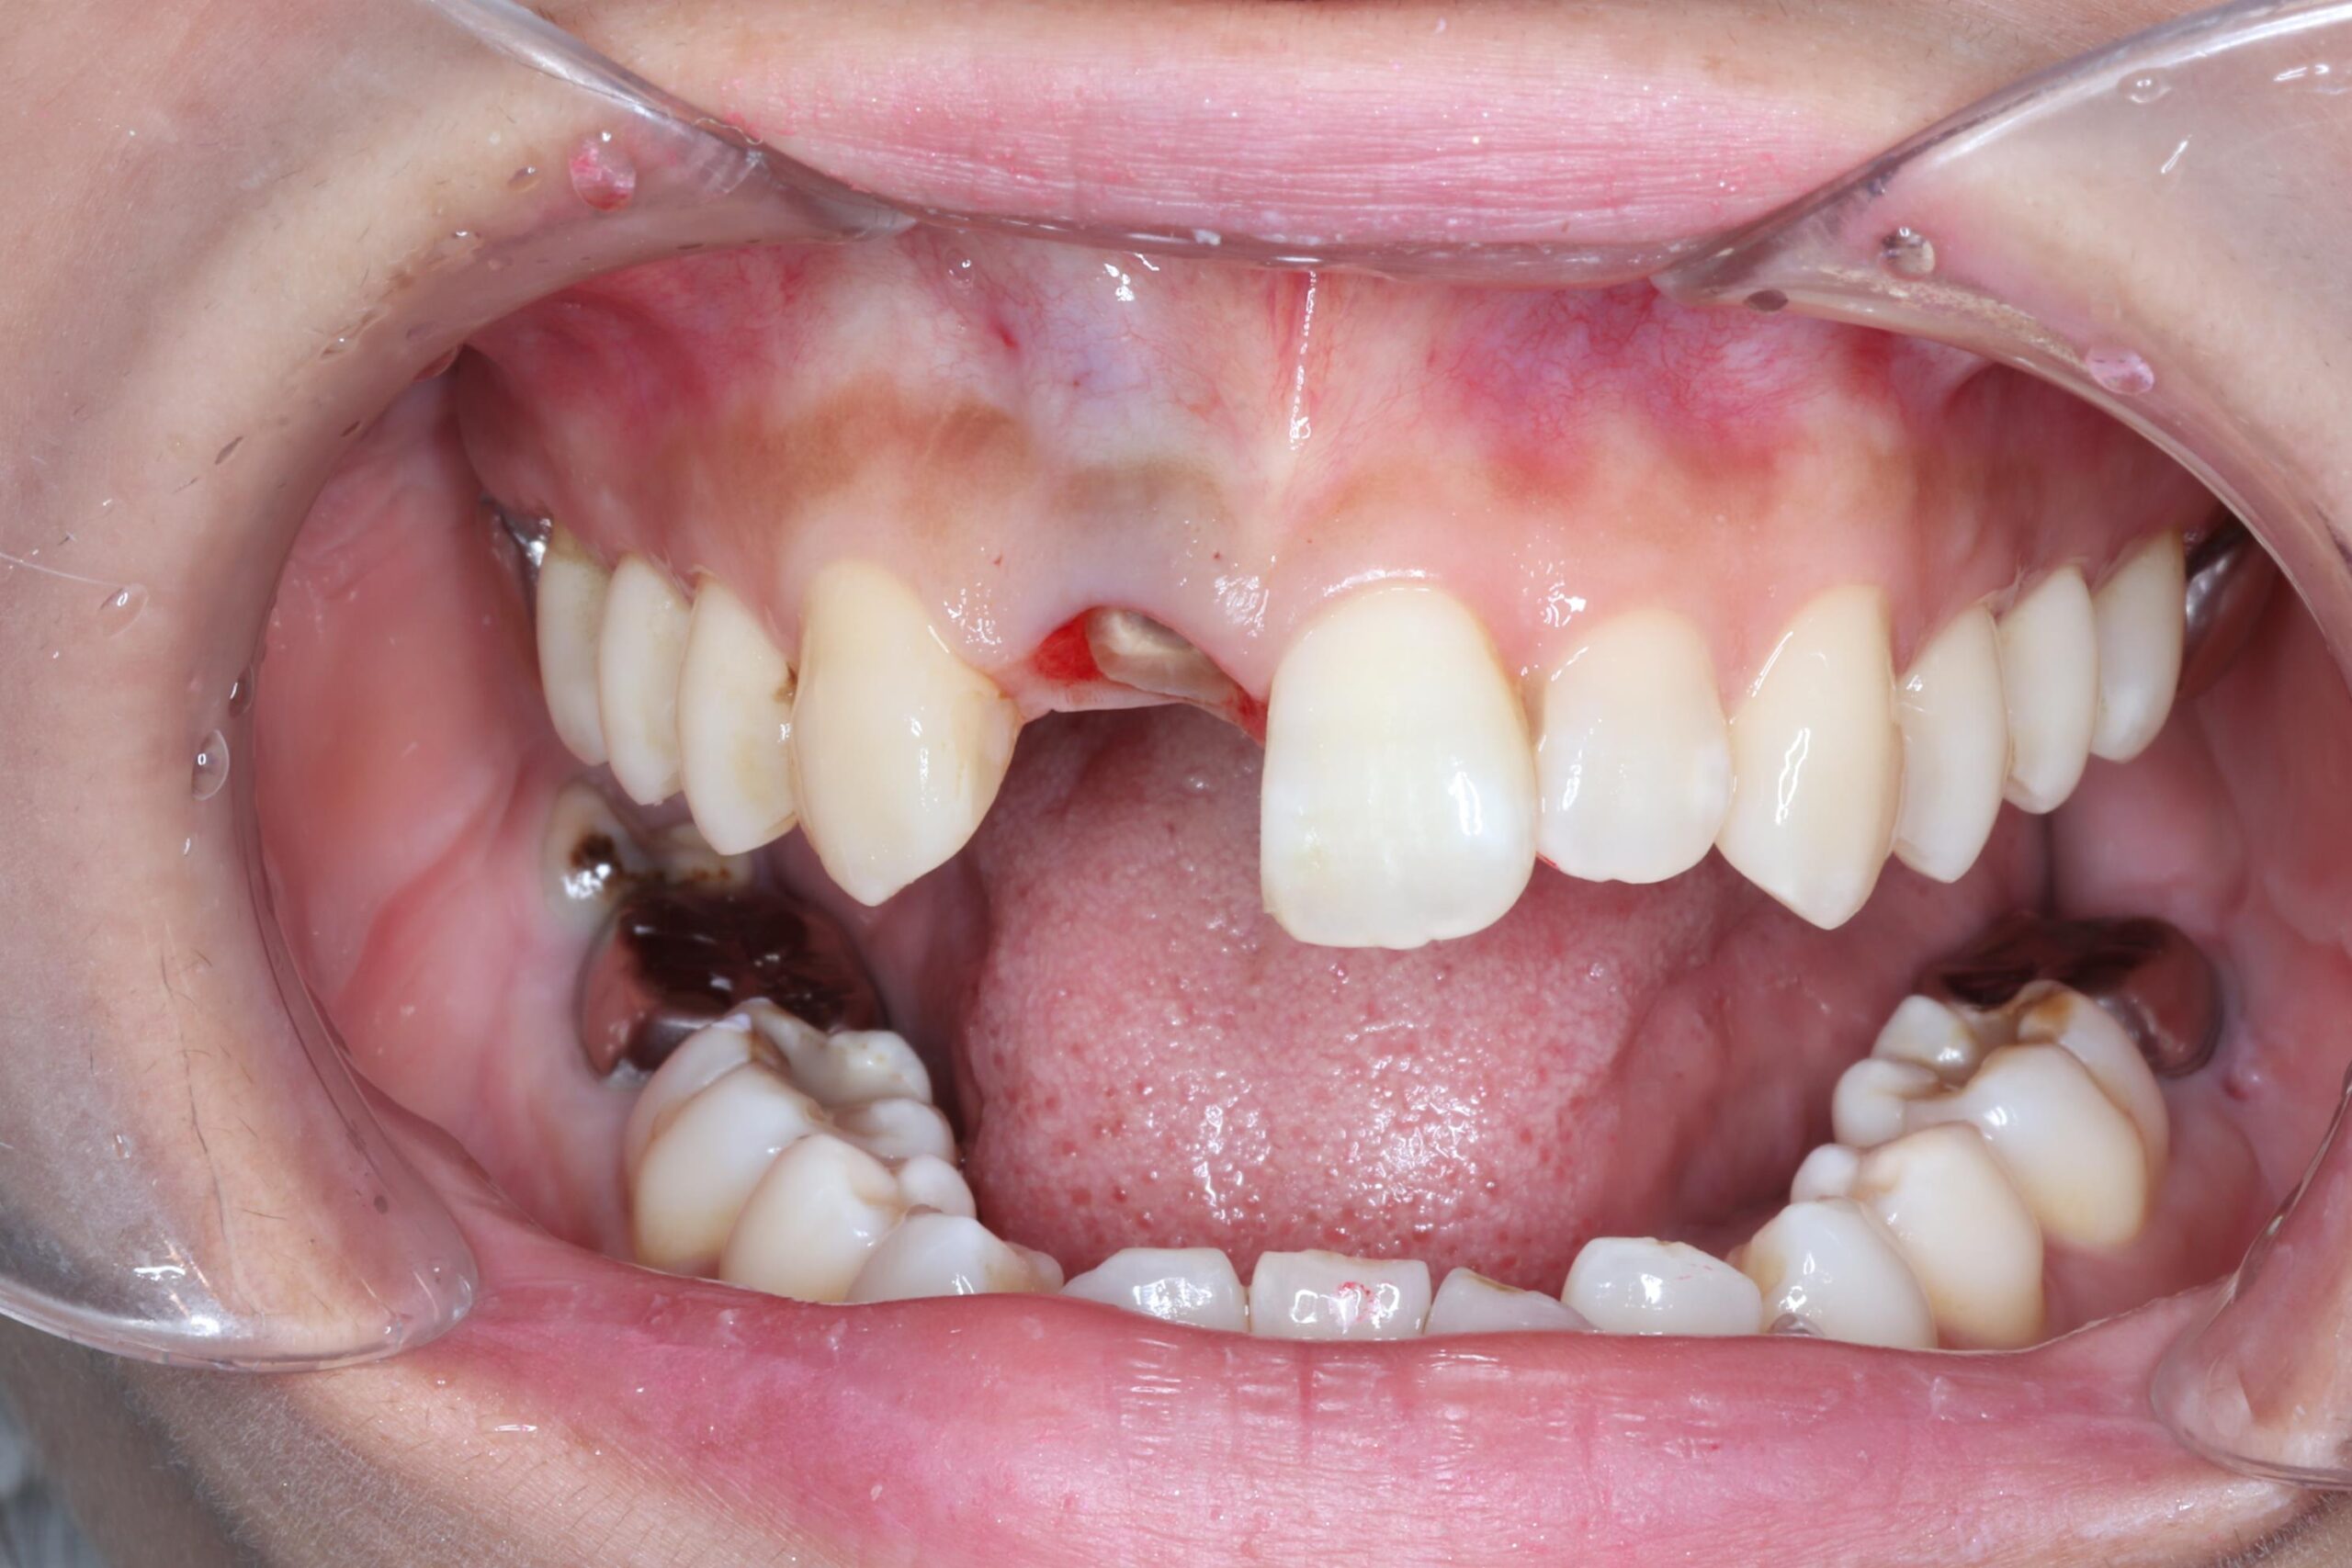

症例12

30代 男性 前歯が折れてしまった。

術前正面観

術後正面観

術前 レントゲン

術後 レントゲン

| 主訴 | 前歯の差し歯が折れてしまい、腫れて痛みがある。できるだけ隣の歯を傷つけずに治したい。 |

|---|---|

| 年代・性別 | 30代 男性 |

| 治療部位 | 上顎左側 1 |

| 治療費用 | インプラント手術料 300,000円 |

| 手術回数 | 1回 |

| 治療期間 | 6ヶ月 |

| 手術時間 | 90分 |

| 治療回数 | 4回 |